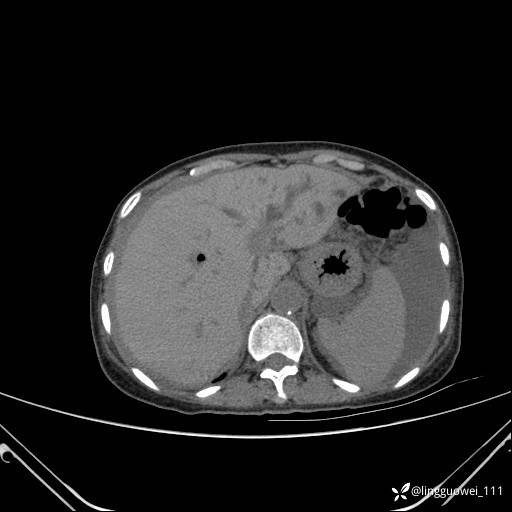

病例女,65岁,门诊行胃肠镜检查后,说腹胀入院检查,CT能发现病因吗?已公布结果

主诉:门诊行胃肠镜检查后,诉腹胀,入院检查,肝有病变吗?腹膜及腹腔的表现有特征性吗?

平扫: